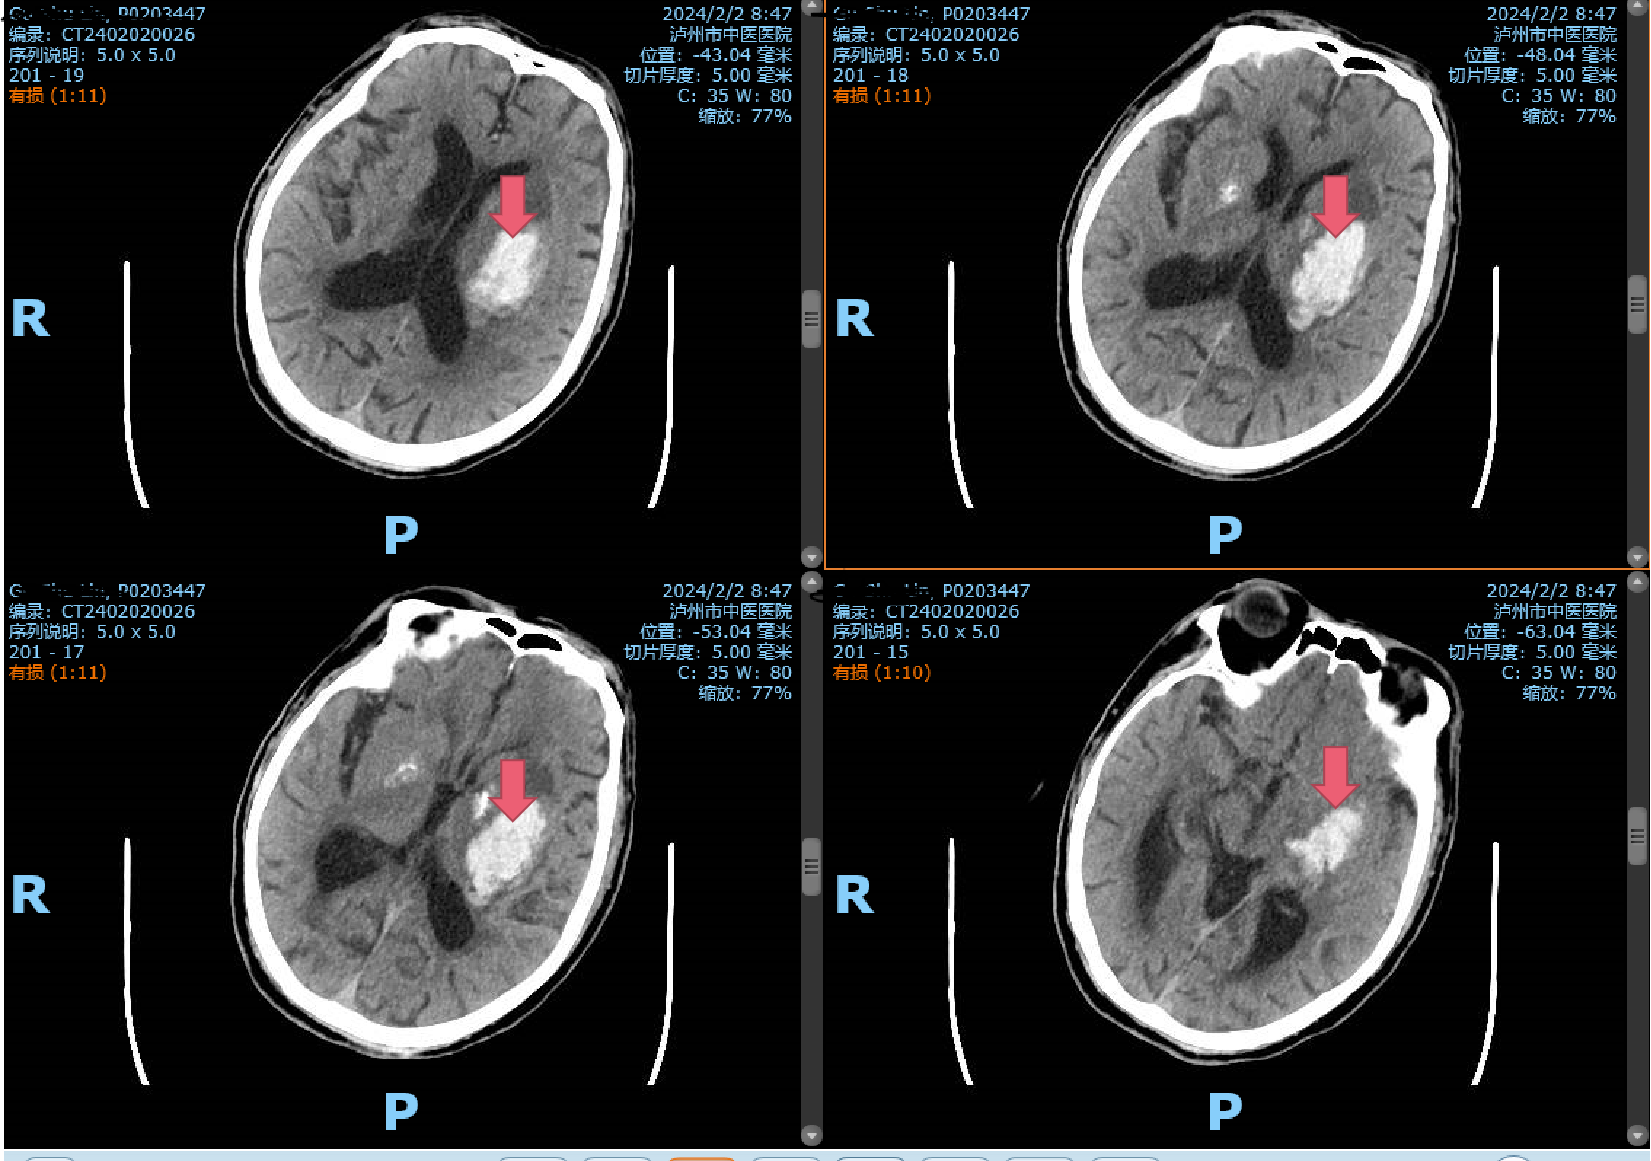

2月2日一早,一陣急促的響鈴聲打破了清晨的寧靜,一位年逾古稀的辜先生在洗澡時(shí)突發(fā)一側(cè)肢體無力,家屬見狀不知所措,焦急萬分,情急之下將患者背下樓,直接送入瀘州市中醫(yī)醫(yī)院急診科!時(shí)間第一,生命至上。患者入院后直接經(jīng)急救通道,完善頭顱CT,提示腦出血,病情危重,立即及時(shí)、安全地送到了市中醫(yī)院重癥監(jiān)護(hù)室,并...